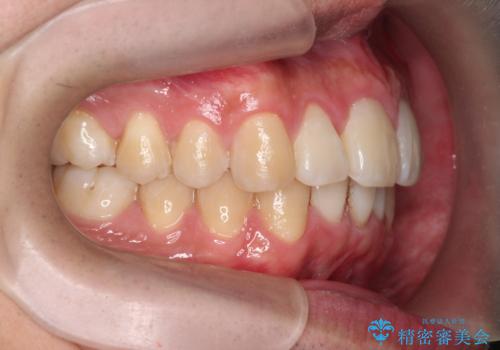

マウスピース矯正で前歯の角度、ガタガタをきれいに

- 突き出た前歯の角度、歯ブラシのしづらい前歯のがたつきの改善を希望され来院されました。

4本の小臼歯を抜きワイヤー矯正治療、下顎前歯を1本抜去しマウスピース治療のメリットデメリットを検討・相談し、より歯を抜く本数の少ないマウスピース矯正を行うこととなりました。

下顎の前歯は1本だけ抜去せざるをえませんでしたが、4本の小臼歯抜去とマルチブラケット矯正を回避することができ、治療結果・過程に満足いただくことができました。